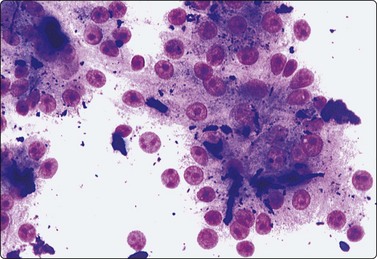

Malignant lymphoma183,184

Liver involvement in stage IV malignant lymphoma portends a poor prognosis and has been found in 25% of random FNA biopsies in patients with lymphoma.185 Primary involvement of the liver is relatively rare. It is often patchy and microscopic and may be missed by either FNA or CNB. The liver tumor may be solitary, multiple or diffuse. Aspirates are usually markedly cellular with dispersed cells and scattered small aggregates without true cohesion, and lymphoglandular bodies are present in the background. Non-Hodgkin lymphoma of diffuse large B cell type (high grade) is the most common type. If on-site rapid evaluation detects a lymphoid lesion, a further needle pass should be performed to obtain cells for phenotyping by immunocytochemistry or flow cytometry, for cytogenetics and for molecular gene rearrangement studies. For detailed cytological criteria for the diagnosis of lymphoma, see Chapter 5. The differential diagnosis of a post-transplant lymphoproliferative disorder (PTLD) should be considered where there is a history of organ transplantation. The smears may be either polymorphous with a mixture of lymphocytes, plasma cells and histiocytes, or monomorphous with large atypical lymphocytes. The diagnosis is supported by identifying B-cell monoclonality and the presence of EBV DNA.183,186,187